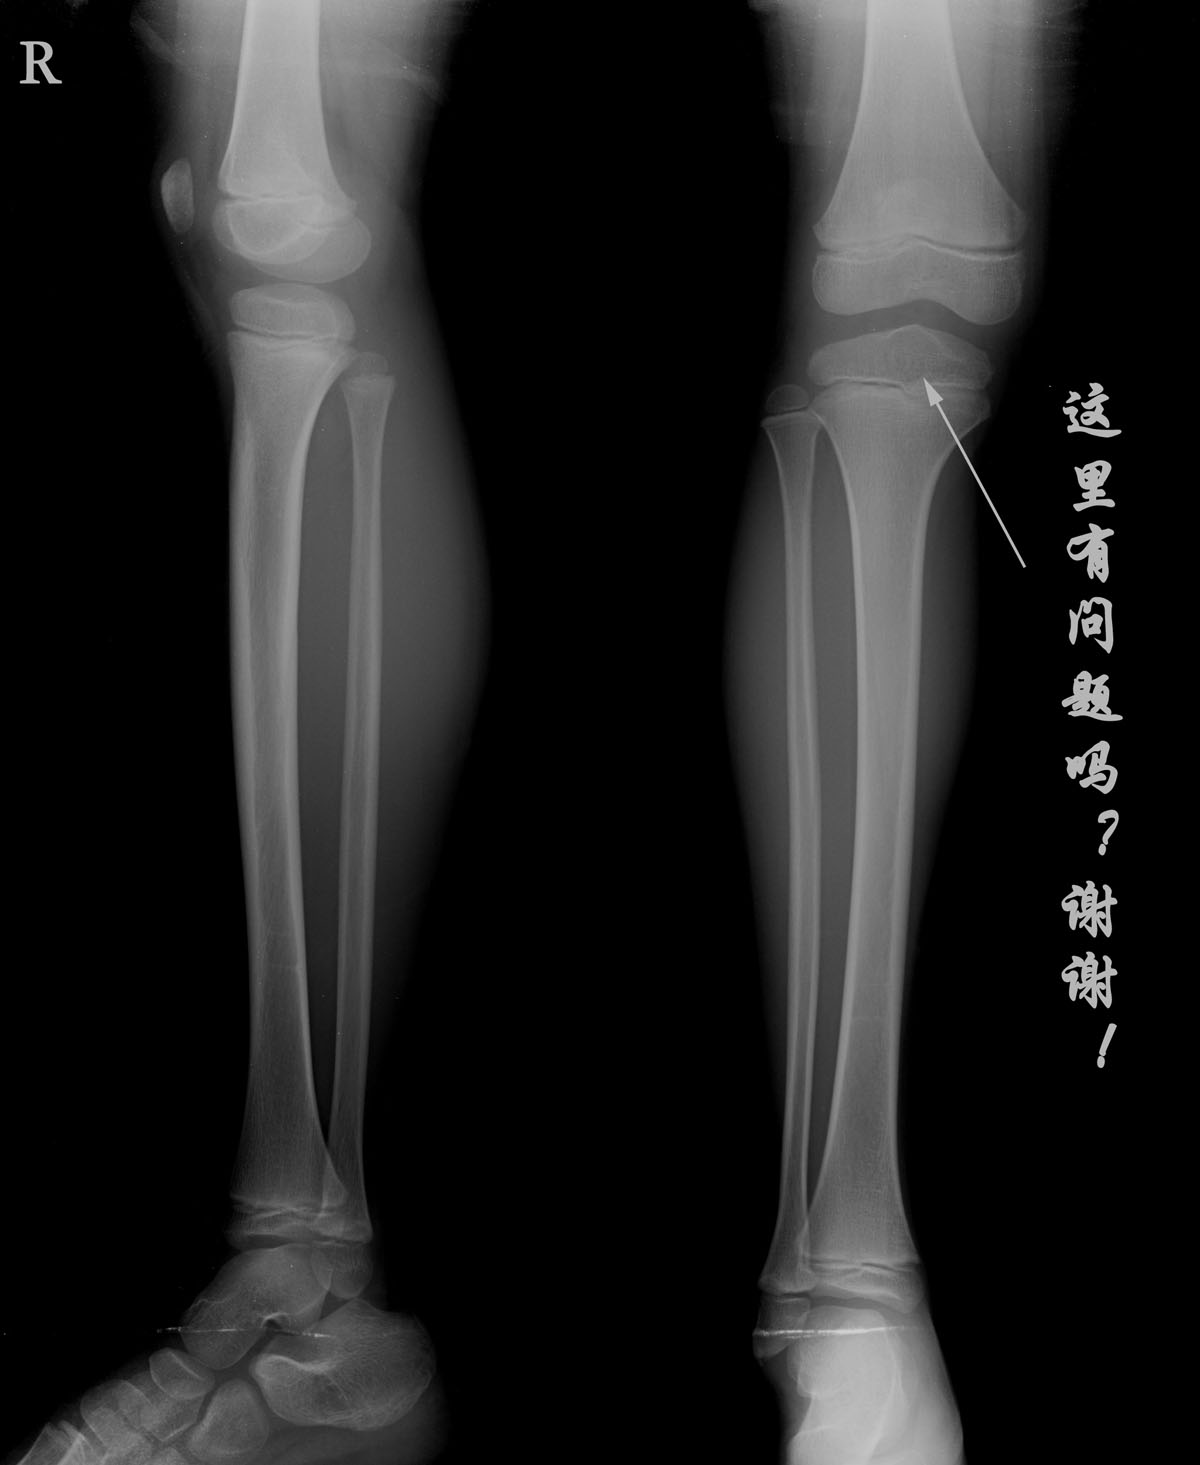

标题: PED1651:男,7岁,外伤右小腿疼痛拍片。 [打印本页]

标题: PED1651:男,7岁,外伤右小腿疼痛拍片。

男,7岁,外伤右小腿疼痛拍片。右膝关节平时无症状。

加照对侧----对比后再定

小孩子的骨片,最好照双侧